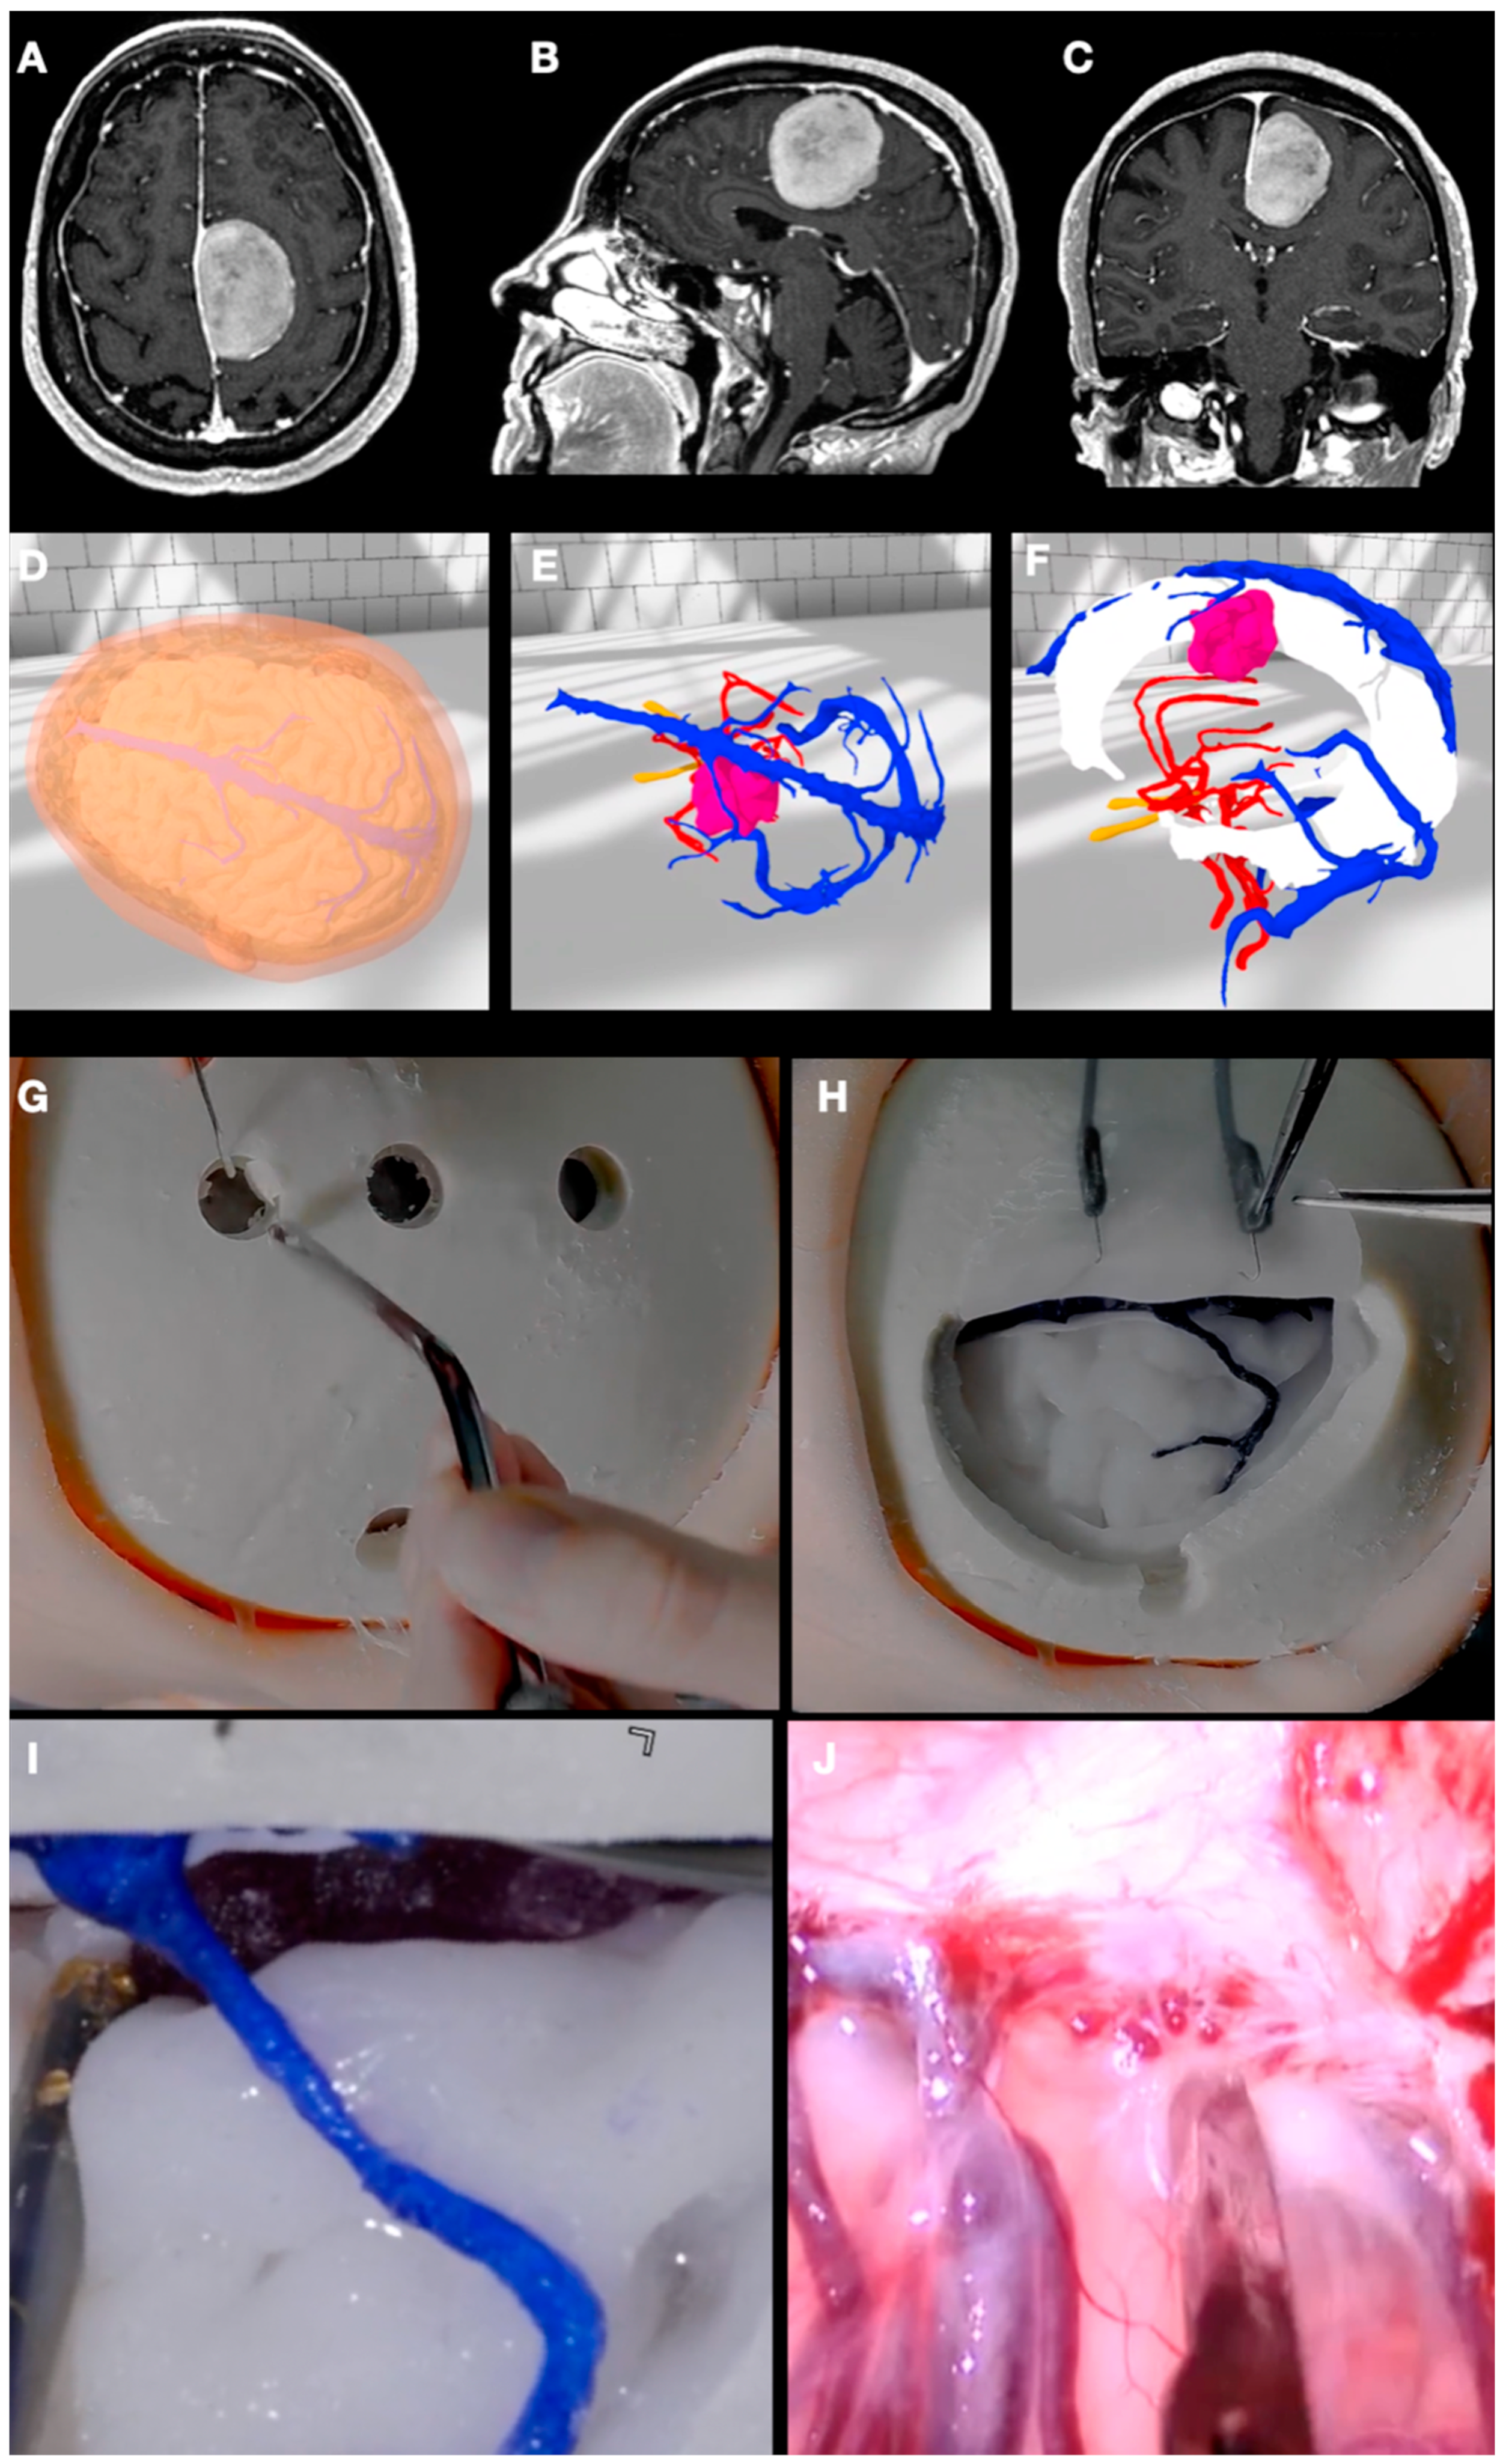

3.5. Case 5: Falcine Meningioma